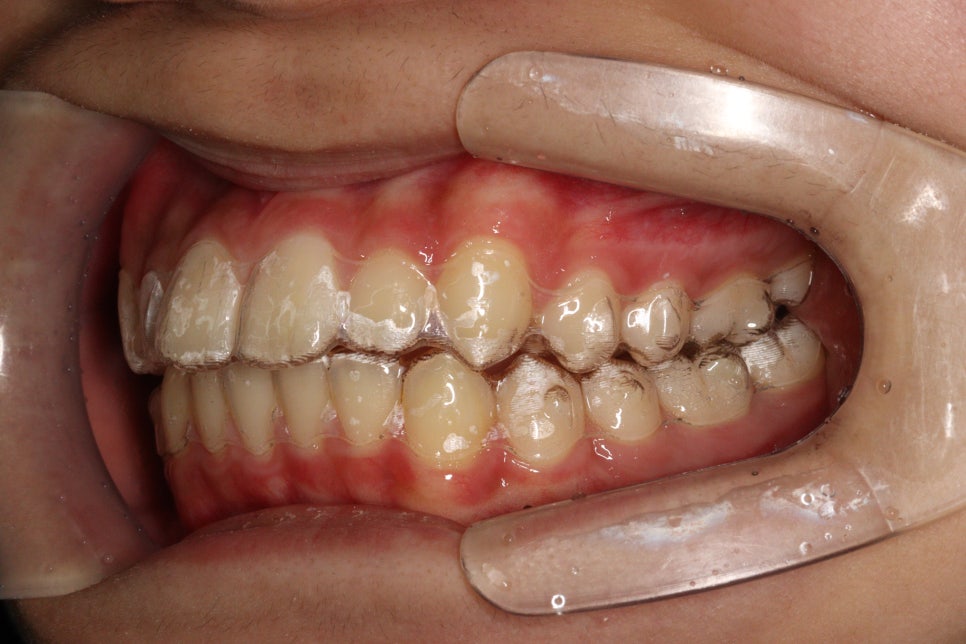

치료 전과 후 입니다.

앞니가 후방이동 한것이 확인됩니다.

우리는 부분교정을 한것이 아니라 간단한 전체교정을 한것입니다.

치아가 들어가보입니다.

앞니만 철사를 붙여서는 얻기 어려운 결과라고 생각합니다.

치료기간 2023.6.20.~2023.12.23.

제작기간 약 1개월

치료기간 약 4개월